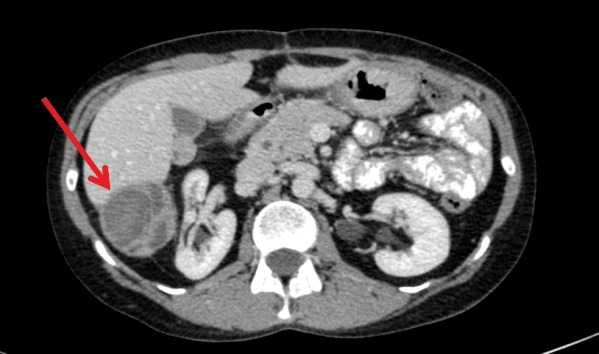

Уточнить величину, локализацию, распространение, характер роста, наличие некротизированной ткани, абсцесса, инфильтрацию в органы – позволяют современные методы рентген-диагностики:

- Компьютерная мультиспиральная томография